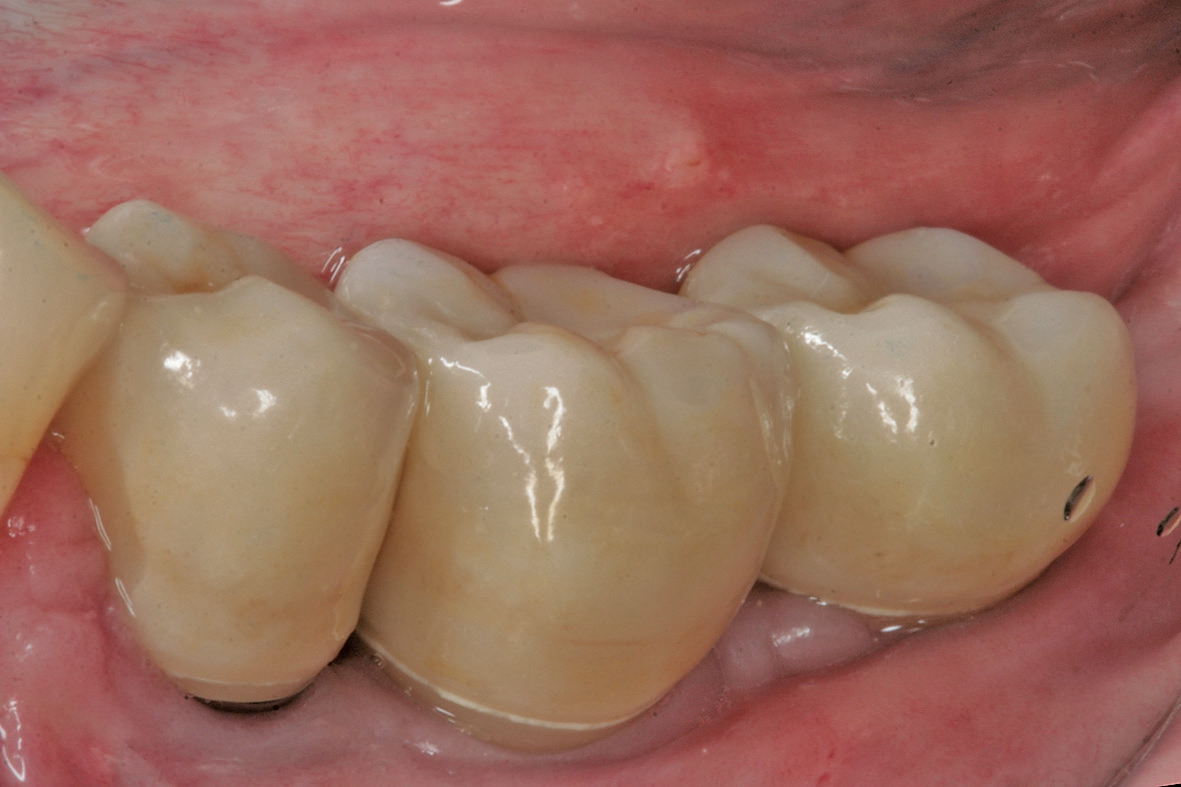

Beim Fehlen von mehreren Zähnen können unterschiedliche Planungs- und Versorgungskonzepte zur Anwendung kommen. Zur Kompensation der geringeren Verankerungsfläche von kurzen Implantaten im Knochen wird neben der Zahn-für-Zahn-Versorgung eine Verblockung von multiplen Implantaten empfohlen [6]. Die Empfehlungen sind aber im Kontext der jeweiligen Implantat- Aufbau-Verbindung, die bei der Versorgung von kurzen Implantaten zur Anwendung gekommen ist, zu berücksichtigen. Aus dem Anwendungsbereich der Implantate mit einer externen Implantataufbauverbindung wird eine Verblockung angeraten, um eine ausreichende Stabilität besonders bei einer hohen Aufbauhöhe des Zahnersatzes sicher zu stellen [6]. Die Erfahrung bei der Anwendung von Implantaten mit einer konischen Implantataufbauverbindung hat gezeigt, dass sich multiple Einzelkronen langzeitstabil eingliedern lassen [2] (Abb. 9-14). Besonders in Hinblick auf das periimplantäre Knochenniveau wird davon ausgegangen, dass sich bei der Einzelversorgung keine Spannungen auf Grund einer unzureichenden zahntechnischen Herstellungsgenauigkeit ergeben können.

Zeigt sich im Rahmen der Planung, dass das vertikale Knochenangebot nur in einem Bereich des zahnlosen Kieferkammabschnittes vorliegt, können kurze Implantate auch mit längeren Implantaten kombiniert werden. Dann kann anstelle der multiplen Einzelversorgung auch eine Brückenversorgung angegangen werden (Abb. 15-18). Bei der Verblockung von Implantaten mit einer konischen Implantataufbauverbindung muss auf eine genaue Übertragung der Implantatanschlussgeometrie geachtet werden, da es durch die Toleranzen bei der Herstellung des Konus zu einem vertikalen Versatz kommen kann. Im Vergleich zu Implantaten mit einer zylindrischen, parallelen Verbindung fehlt hier der Anschlag, der eine genaue Übertragung der vertikalen Position sicherstellt. Um diesen vertikalen Fehler zu vermeiden empfiehlt es sich auf Abutmentniveau abzuformen. In diesem Fall kann das Abutment auch in-situ verbleiben, so dass das periimplantäre Weichgewebe nicht mehrfach traumatisiert wird.